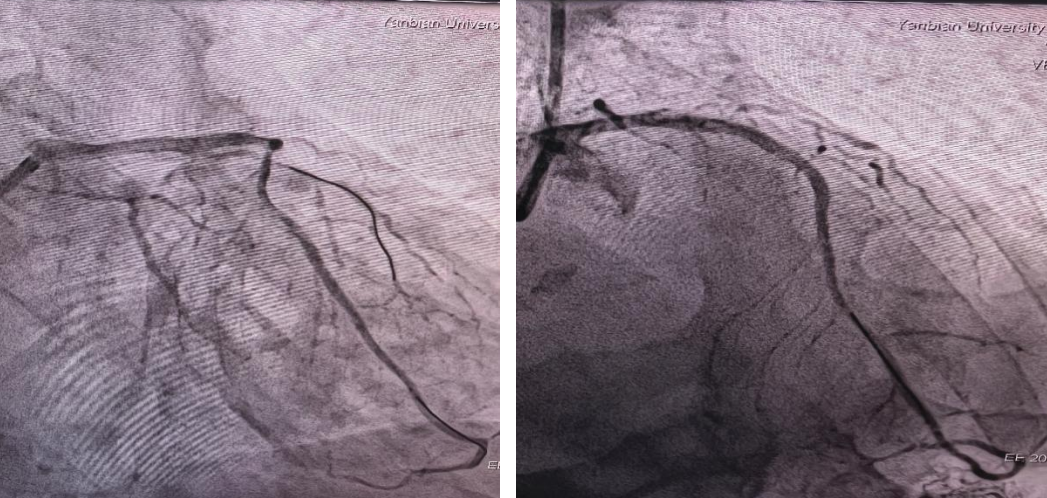

术前造影图像

术后造影图像